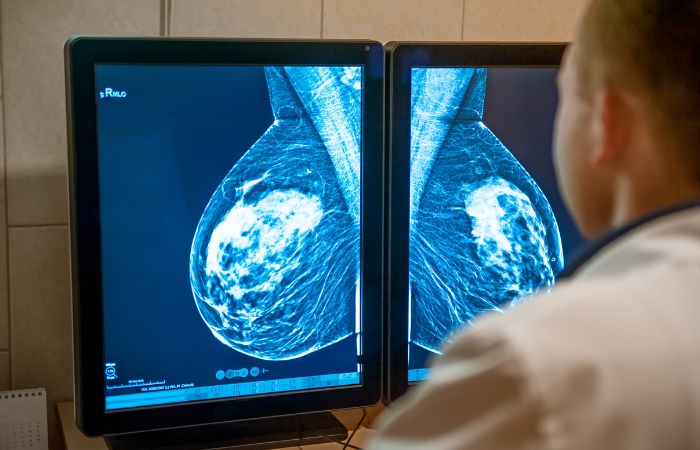

Early detection saves lives. A mammogram is a low-dose X-ray that can find breast changes even before symptoms appear.

A mammogram is an X-ray of the breast tissue used to detect early signs of breast cancer, such as tumors or abnormalities. This test can identify changes in the breast tissue even before any symptoms are noticeable, which is why regular mammograms are essential for women, especially those in higher-risk categories.